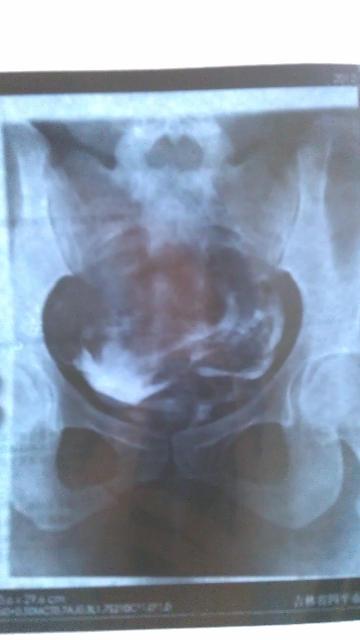

患者信息:女 28岁 病情描述(发病时间、主要症状等):表现:注入造影剂后,宫腔充盈,子宫影大致呈三角形位置偏左,边缘光滑。两宫角充盈可, 双侧输卵管在宫旁连续显示,边缘光滑,造影剂经双侧伞端溢入盆腔,并可见少许弥散。第三张片显示盆腔内见有游离造影剂。诊断:子宫影显示正常,双侧输卵管通畅。 本人月经正常,周期27-28天,卵泡监测排卵正常,大小在2.0*1.9左右想得到怎样的帮助:结婚一年一直没有宝宝,去医院做造影后说我盆内输卵管有粘连,医生让我住院治疗两个疗程,我只住院治疗一个疗程,这个月不想去了,我找人说先让我先吃两瓶八珍益母丸,请问看片子我是否还要住院?我是否可以要宝宝了曾经治疗情况及是否有过敏、遗传病史:无